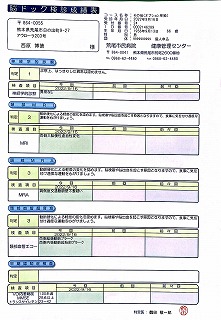

090 脳ドック

2024.18.14 荒尾市民病院 2023.08.10 荒尾市民病院

2024 PDF 2023 PDF

22.9.16 荒尾市民病院